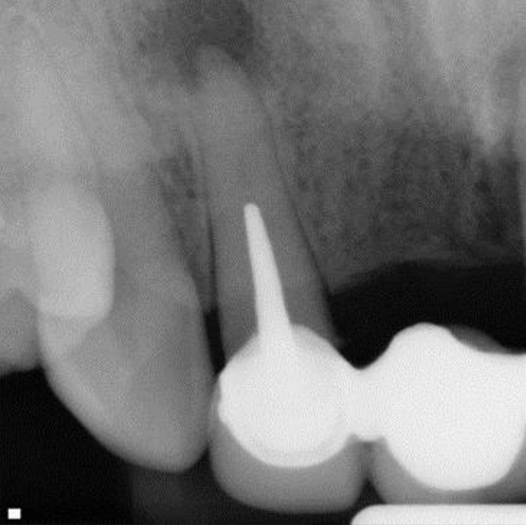

Before

After

Before Root Canal treatment

After Root Canal treatment